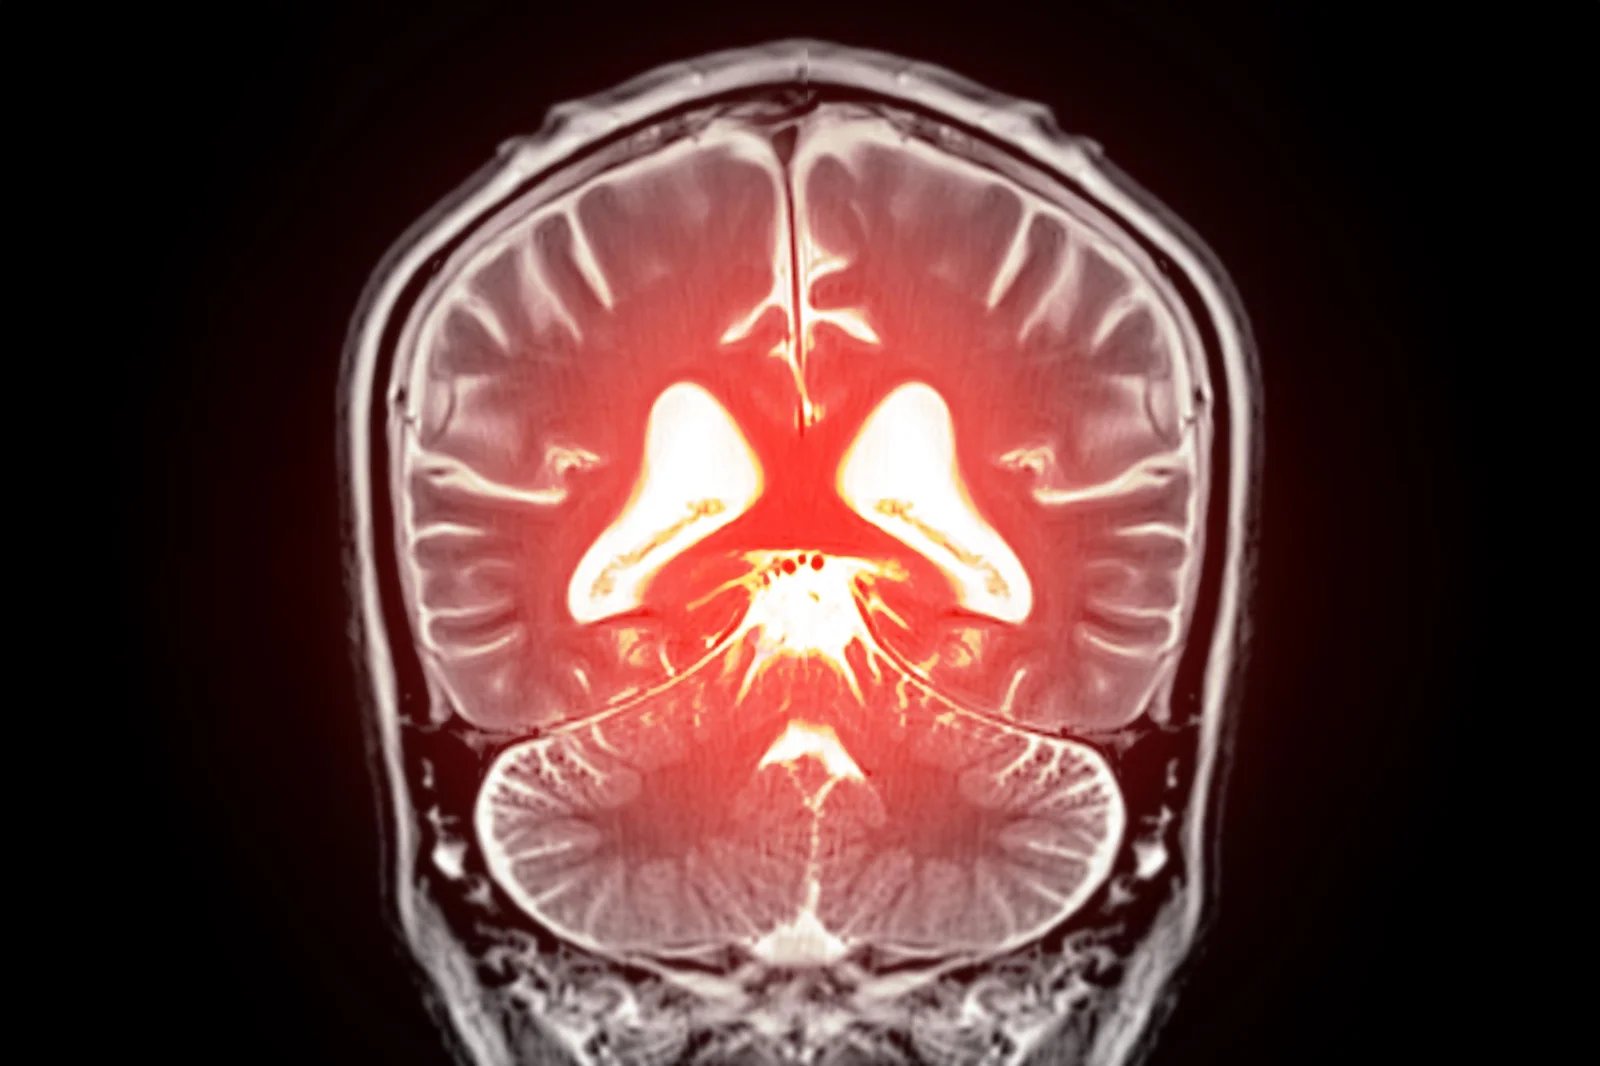

قد يؤدي استبدال الدهون المفقودة في الدماغ إلى تهدئة الأوعية الدموية المفرطة النشاط واستعادة تدفق الدم الصحي، مما يفتح طريقًا جديدًا نحو علاج الخرف.

بدأ يتبلور نهج جديد محتمل لعلاج انخفاض تدفق الدم في الدماغ وبعض أشكال الخرف. كشف علماء في جامعة فيرمونت، روبرت لارنر، دكتوراه في الطب بكلية الطب، تفاصيل جديدة حول كيفية تنظيم تدفق الدم في الدماغ وحددوا استراتيجية يمكن أن تساعد في تصحيح المشاكل في الأوعية الدموية في الدماغ. تم نشر بحثهم قبل السريري اليوم (22 ديسمبر) في وقائع الأكاديمية الوطنية للعلوميشير إلى أن استعادة الفسفوليبيد المفتقد في مجرى الدم قد يساعد في تطبيع تدفق الدم العقلي وتخفيف الأعراض المرتبطة بالخرف.

اكتشف العلماء أن PIP₂ يعمل عادةً كمكابح طبيعية لـ Piezo1. عندما تنخفض مستويات PIP₂، يصبح Piezo1 نشطًا بشكل مفرط، مما يعطل تدفق الدم الطبيعي في الدماغ. عندما أضاف الباحثون PIP₂ مرة أخرى إلى النظام، انخفض نشاط Piezo1 وتم استعادة تدفق الدم الصحي. تشير هذه النتائج إلى أن زيادة مستويات PIP₂ يمكن أن تمثل نهجًا علاجيًا جديدًا لتحسين الدورة الدموية في الدماغ ودعم وظائف المخ.